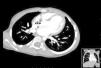

Case 3A 19-day-old baby boy was admitted to a Pediatric Intensive Care Unit following cardiorespiratory arrest of unknown cause. Cardiac catheterization to rule out anomalous coronary artery anatomy was performed and the right ventricular angiogram revealed a fistulous tract between the RV and the pulmonary artery (Figure 3).